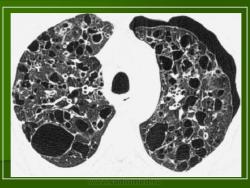

В 5 наблюдениях (21%) из больных с распространенной формой заболевания отмечались изменения в легких в виде обогащения, избыточности легочного рисунка, его деформации по сетчато-петлистому типу, очаговых теней. Корневая и медиастинальная аденопатия отсутствовали. В 1 случае в легких выявлена киста, которая периодически осложнялась нагноением (Рис. 4).

Поражение легочной ткани (рис. 22) свойственно любому возрасту. Часто больные имеют общие симптомы — лихорадку, слабость, реже — кашель, одышку, боли в грудной клетке. На рентгенограммах отмечается деформация и усиление легочного рисунка и микроузловые инфильтративные тени. Поражение костного мозга (с наличием клеток Лангерганса) сопровождается цитопенией периферической крови.

Рис. 22. Поражение легких при Лангер-гансово-клеточном гистиоцитозе.